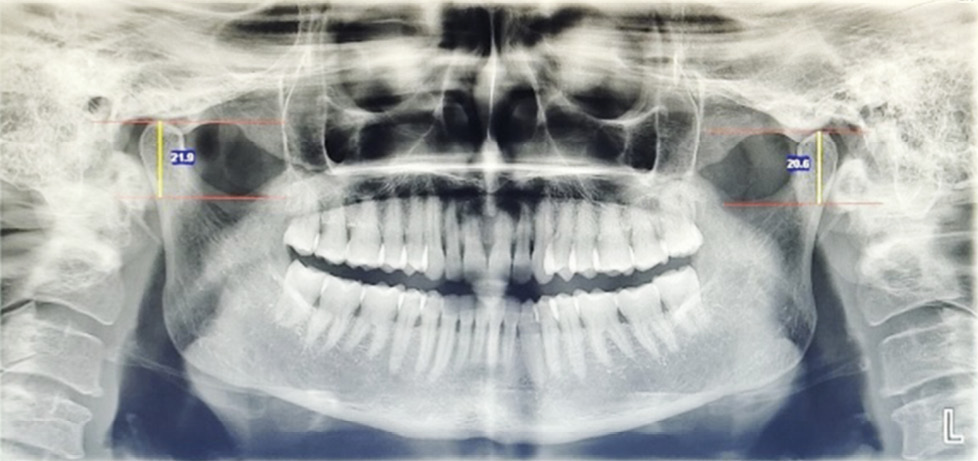

- Condyle length (CL):

Fig. 2. Length of the condyle bilaterally.

It is the distance measured between two tangential lines that are drawn at the superior most point of the condylar head and the deepest point of the concavity of the sigmoid notch.